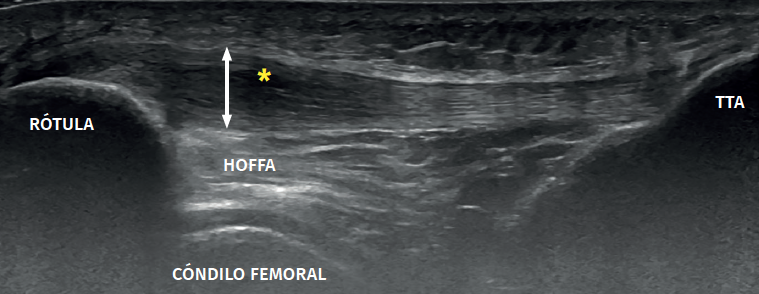

High volume image guided injection (HVIGI) in turn targets neurovascular growth (from the paratendon to the tendon). This technique consists of high volume ultrasound-guided injections at the interface between the patellar tendon and Hoffa's fat pad (10 ml of 0.5% bupivacaine, 25 mg of hydrocortisone and 12-40 ml of physiological saline). The injections produce local mechanical effects, disrupting or occluding the neovessels and their accompanying nerve supply, and are mainly used in PT where conservative management proves insufficient and neovessels are identified by Doppler ultrasound(36).